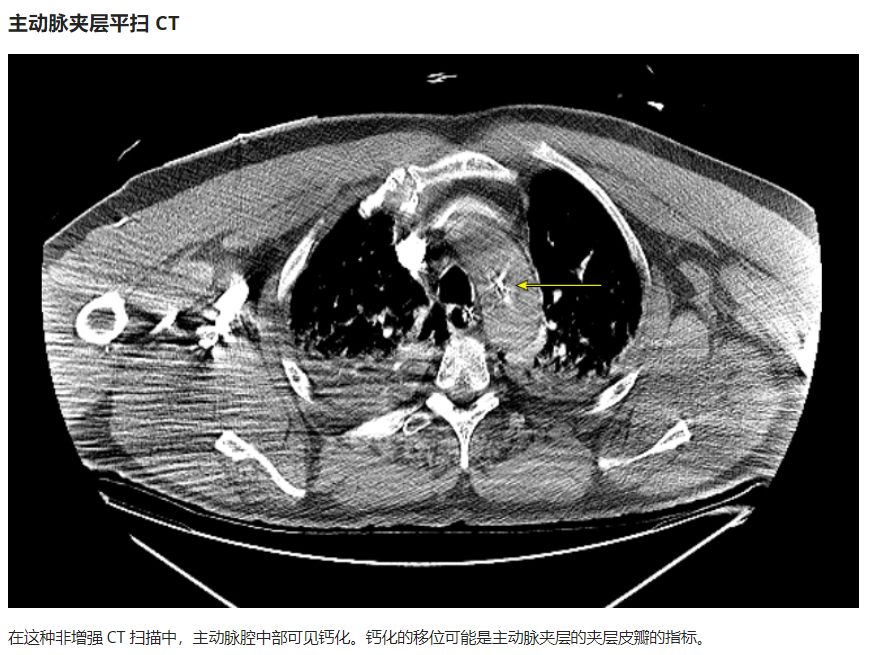

下图的胸部CT平扫,有什么大问题?

仔细一看,主动脉里面有线样高密度阴影!这个要高度警惕主动脉夹层!